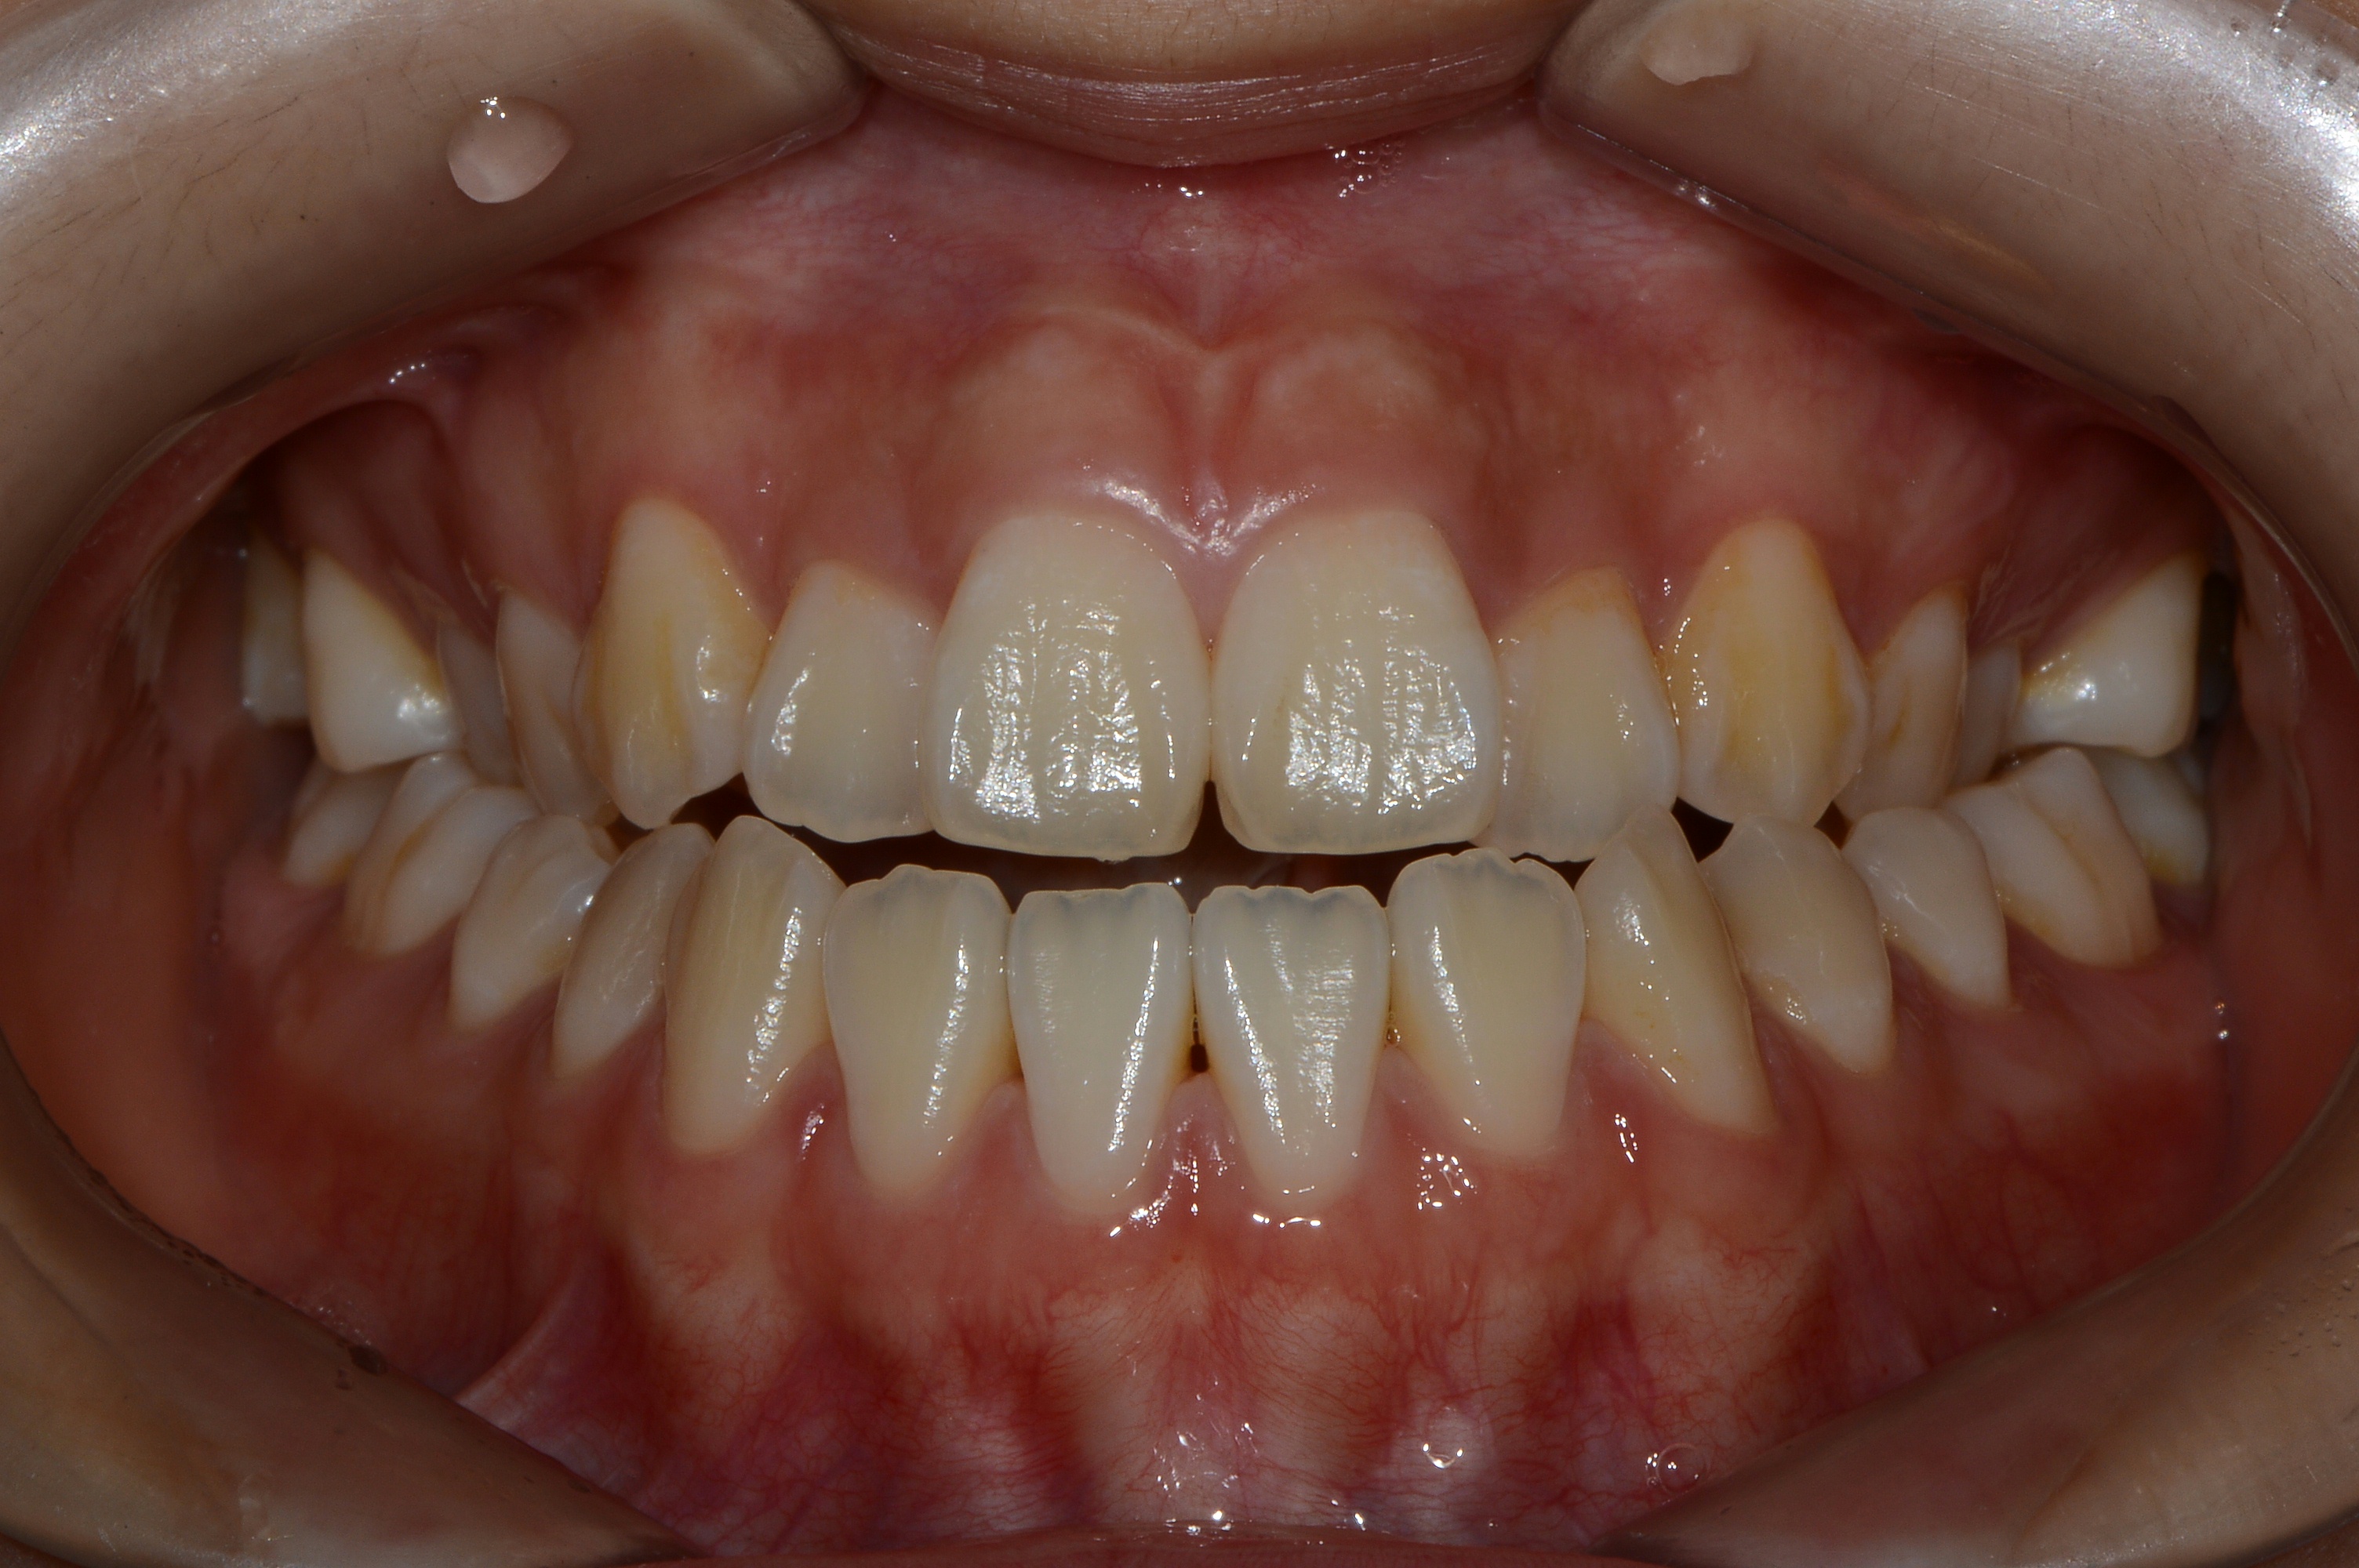

치료 후 사진입니다.